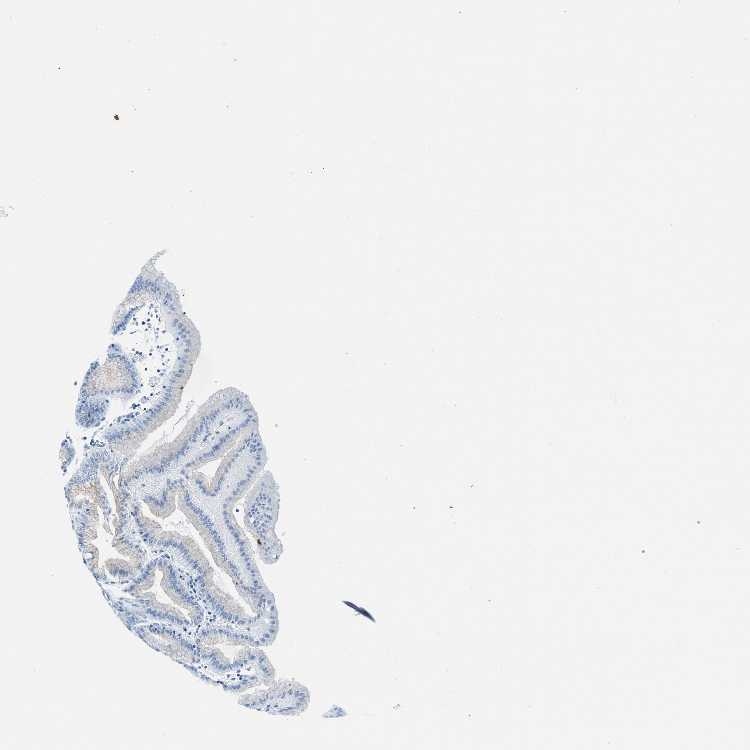

STOMACH 1 - Antibody stainingi

Antibody staining in the annotated cell types in the current human tissue is reported as not detected, low, medium, or high, based on conventional immunohistochemistry profiling in selected tissues. This score is based on the combination of the staining intensity and fraction of stained cells.

Each image is clickable and will lead to virtual microscopy that enables deeper exploration of all samples and also displays staining intensity scores, fraction scores and subcellular localization as well as patient and tissue information for each sample.

Antibody HPA022988Antibody HPA024446

Glandular cells Not detectedHigh